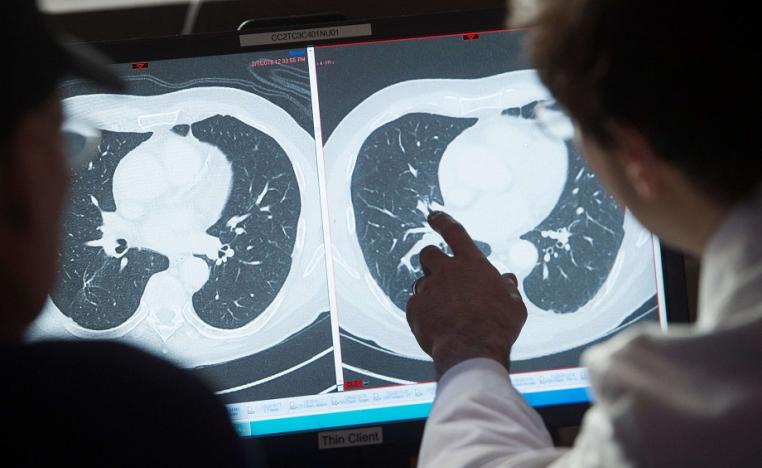

اختبار دم يفضح السرطان يخوض امتحانا نهائيا